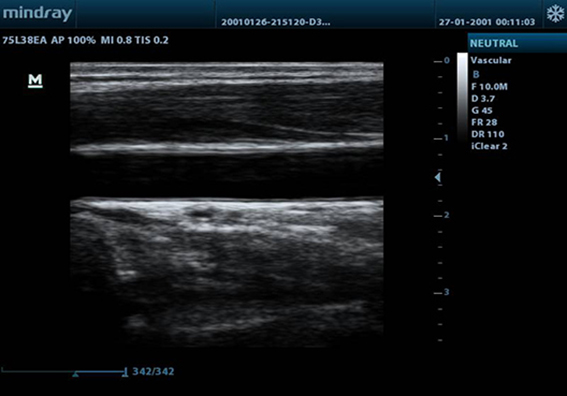

DP-30

Ulasan

Sebuah sistem USG hitam & putih yang efisien, DP-30 dilengkapi dengan teknologi pencitraan canggih untuk memberi Anda gambar berkualitas tinggi dan alur kerja yang efisien yang memungkinkan Anda untuk memindai dengan keyakinan dan kemudahan. Dengan desain yang portable yang ringan dan ergonomis, DP-30 dapat menemani Anda di mana pun diperlukan.

Pencitraan Harmonik Jaringan (Tissue Harmonic Imaging)

Memanfaatkan harmonik kedua yang dihasilkan dari lapisan-lapisan batas jaringan, THI secara signifikan meningkatkan resolusi kontras dan meningkatkan kualitas gambar terutama untuk subyek yang secara teknis sulit.

TSI

Pencitraan Spesifik Jaringan mengoptimalkan kualitas gambar berdasarkan sifat-sifat jaringan yang dipindai. Empat pilihan pencitraan yang tersedia termasuk umum, otot, cairan dan lemak.

iClear?

untuk mendapatkan kualitas gambar yang lebih baik berdasarkan deteksi struktur secara otomatis

Batas gambar yang lebih tajam dan utuh

Jaringan yang homogen seragam dan halus

Jernih